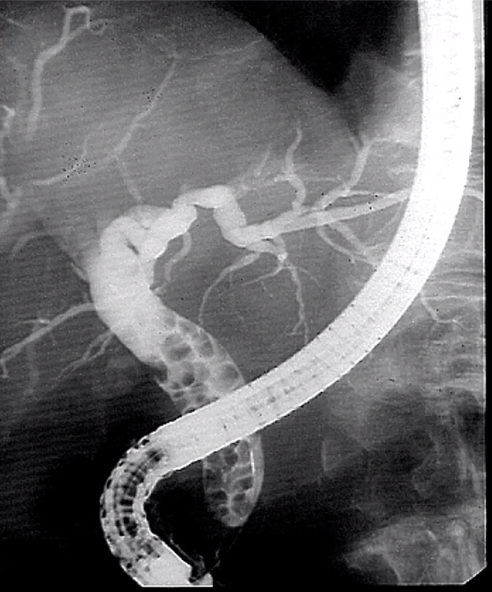

type of imaging

what is shown

ERCP - Endoscopic Retrograde Cholangiopancreatography + cholangiogram